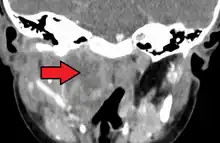

A computed tomography (CT) scan is the definitive diagnostic imaging test.[6]

Large retropharyngeal abscess as seen on CT